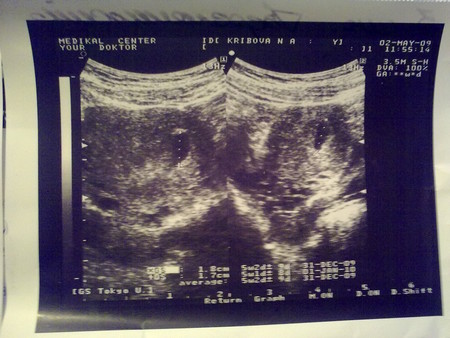

Результаты УЗИ Угроза!!!

Девочки может кто знает подскажите что делать!! С первой беременностью такого не было! Послед менстр 23.03.09 акушерский срок 7 нед.

1 узи 02.05.09 срок 5 недель

2 Узи 04.05.09

Матка: отклонена: вправо 56*48*55

Структура миометрия: однородная

Полость матки: расширена до 4,8 - 5,0мм

Плодное яйцо: визуализируется в н/трети полости

размерами 3,7*2,8*3,6 мм ср.диаметр 3,36 мм

яичники

правый б/о

левый содержит желтое тело 18*14

область малого таз б/о

Заключение: Беременность м. срока (Плодное яйцо не соотвестсвует сроку 5 недель) Угроза выкидыша